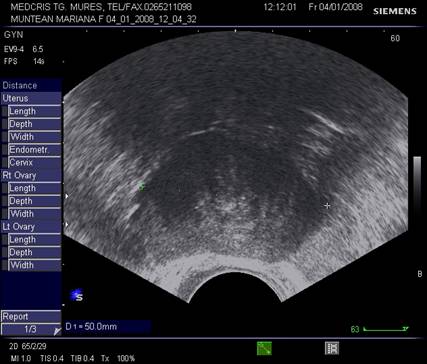

Fig. Nr.378. Pacienta

cu fibromatoza uterina difuza la ecografia transvaginala , dupa miomectomie . (

se remarca ecostructura uterina cu travee multiple cu ecogenitate crescuta, in

special in peretele anterior uterin)